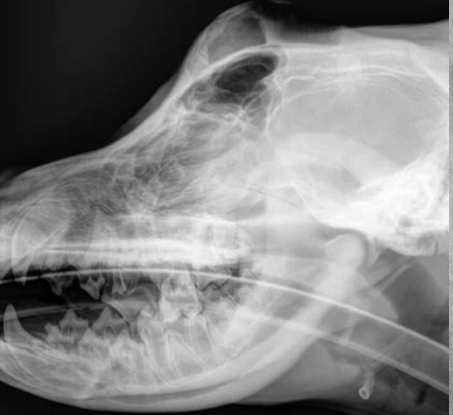

Describe a good Lateral skull view.

Superimposition of structures on both sides.

- Good land marks: check that mandibles and aural bullas are overlaid.

Use pads/foams to support nose and/or jaws.

Nose (mid-sagittal plane) parallel to table.

You can do open mouth or closed mouth.